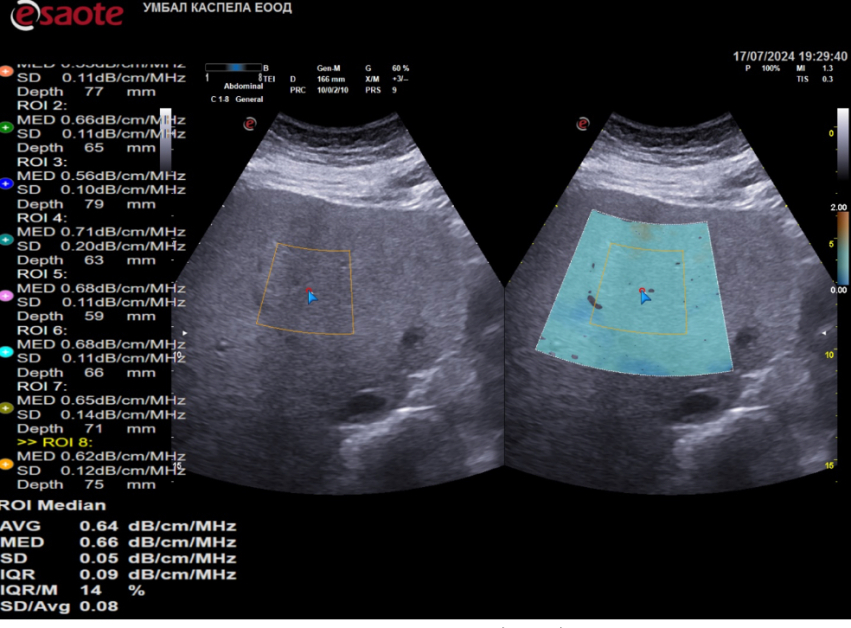

Клиниката по гастроентерология на УМБАЛ Каспела разполага с ехографски апарати от последно потомство на водещи производители- Hitachi Aloka, Philips, Esaote. Освен рутинната ехография те оферират и програмен продукт за качествена и количествена оценка на чернодробната стеатоза и фиброза- pSW и 2D еластография, QAI - количествена оценка на чернодробното омазняване.

Ехографското проучване посредством тези способи е бързо, безболезнено за пациента и без дискомфорт или лъчево натоварване.

Диагностицирането на чернодробната стеатоза и инфектиране постоянно стартира с ехографски обзор и лабораторни проби.